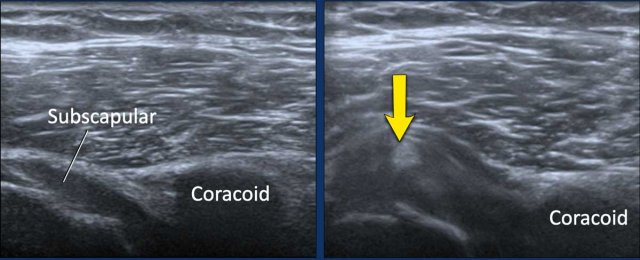

Image during exoratation (left) and endorotation (right) Image during exoratation (left) and endorotation (right)

Impingement

During endorotation a normal subscapular tendon should show almost complete passage underneath the coracoid process.

Impingement is suspected when a residual portion of the tendon is still visible during maximum endorotation.

Images

During endorotation there is incomplete passage under the coracoid and buckling of the subscapular tendon.